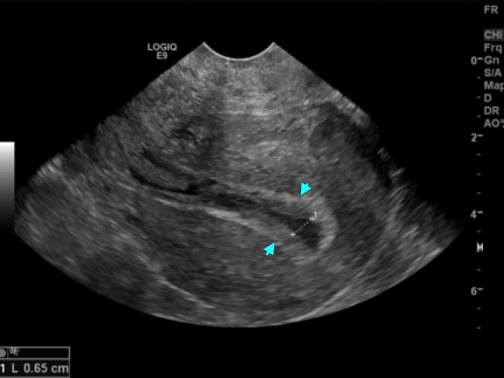

Узи после эко день

Узи после эко день 113 фотографий